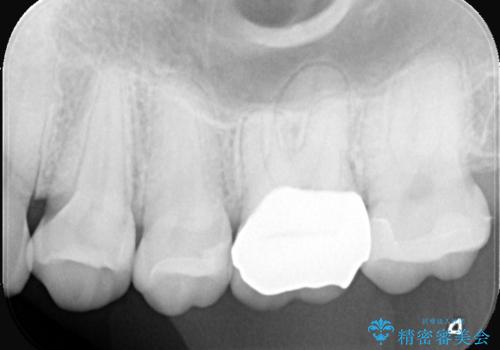

今回の治療では、虫歯の大きさや深さに応じて、異なるセラミック修復法を適用しました。

比較的軽度な虫歯には、セラミックインレー(詰め物)で対応し、健全な歯質を最大限に残しました。

進行した虫歯や歯の強度が低下している歯には、セラミッククラウン(被せ物)を選択し、歯全体を保護することで破折を防ぎました。